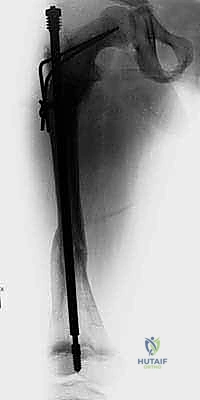

الدليل التفصيلي لخطوات العملية الجراحية: بضع العظم عبر الجلد والمسامير التلسكوبية

تُعد هذه العملية من أدق العمليات في جراحة عظام الأطفال، وتتطلب مهارة استثنائية كما هو الحال مع البروفيسور محمد هطيف. يتكون المسمار التلسكوبي (Fassier-Duval) من جزأين يتداخلان ببعضهما البعض (مثل التلسكوب). يتم تثبيت أحد الأطراف في أعلى العظم والطرف الآخر في أسفله. عندما ينمو العظم، ينزلق الجزء الداخلي من المسمار للخارج، مما يسمح للعظم بالنمو الطبيعي دون أن ينثني أو ينكسر.

الخطوة الرابعة: إدخال المسمار التلسكوبي

بعد تقويم العظم وجعله مستقيماً كحبات المسبحة على خيط، يتم إدخال السلك الدليلي (Guide Wire). ثم يتم إدخال الجزء الخارجي (الأنثوي) من المسمار التلسكوبي وتثبيته في الجزء العلوي من العظم (Epiphysis).

بعد ذلك، يتم إدخال الجزء الداخلي (الذكري) من المسمار عبر الجزء السفلي من العظم وتثبيته في المشاشة السفلية. هذا التصميم العبقري يضمن حماية العظم بالكامل من الداخل.